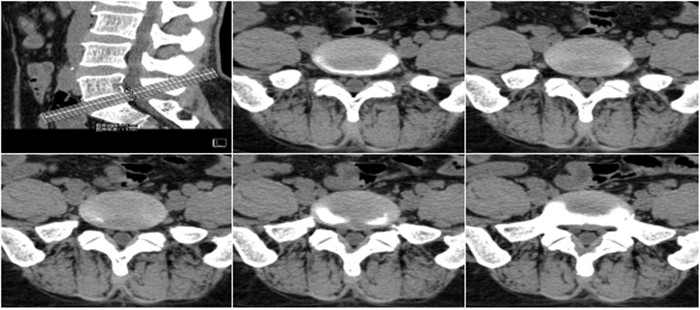

明峰CT搭載了領(lǐng)先的硬件技術(shù)平臺(tái)及系統(tǒng),強(qiáng)大的掃描能力可滿(mǎn)足臨床的各種要求,呈現(xiàn)更極致的細(xì)節(jié),為各臨床科室提供高品質(zhì)的圖像。薄層掃描,消除部分容積效應(yīng),提高各向同性。配合高分辨率算法,有助于細(xì)微結(jié)構(gòu)和形態(tài)學(xué)顯示。